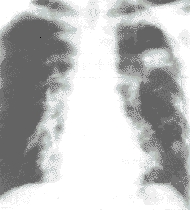

轻微的鸡胸往往不就诊,较重的鸡胸畸形明显,临床上很容易确诊,侧位X线胸片能清楚显示胸骨的畸形状况,其他检查方法常无异常发现。